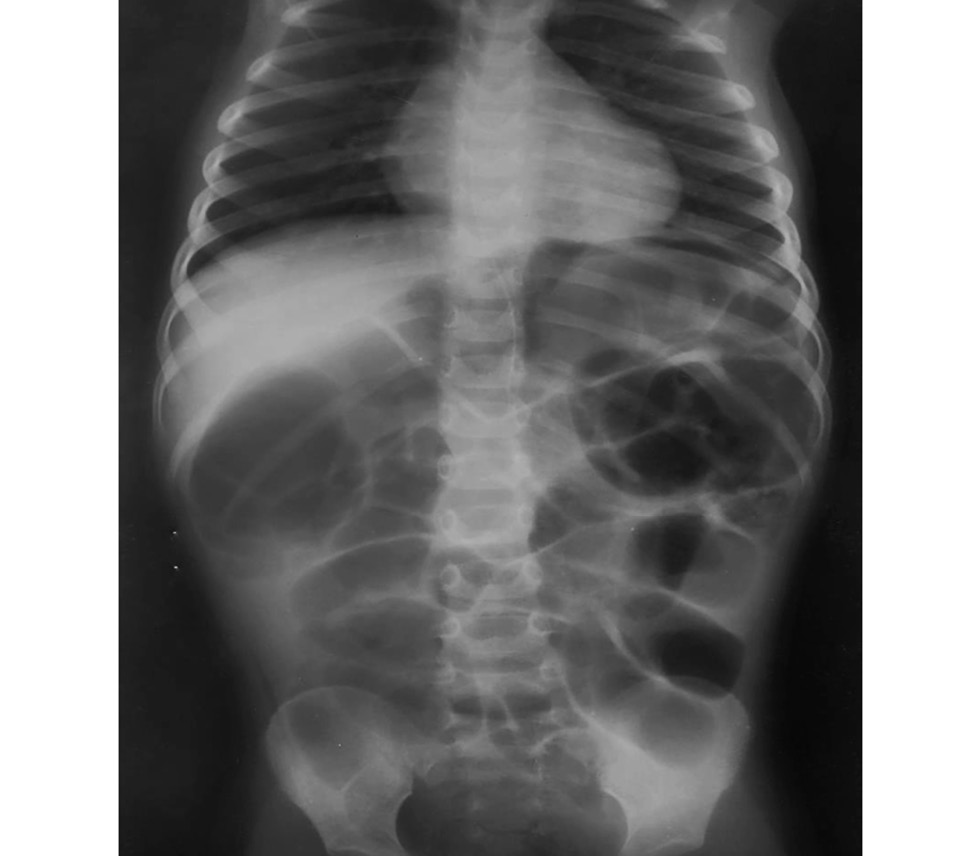

Рентгеноскопия кишечника: через 6 ч после перорального введения бариевой взвеси выявлены множественные чаши Клойбера, следы контраста в кишечнике, свободный газ под куполом диафрагмы (рис. 2).

Рис. 2. Картина непроходимости и перфорации полого органа: выявлен свободный воздух под куполом диафрагмы.

Fig. 2. Obstruction and perforation of the hollow organ is visible: free air under the dome of the diaphragm is revealed.